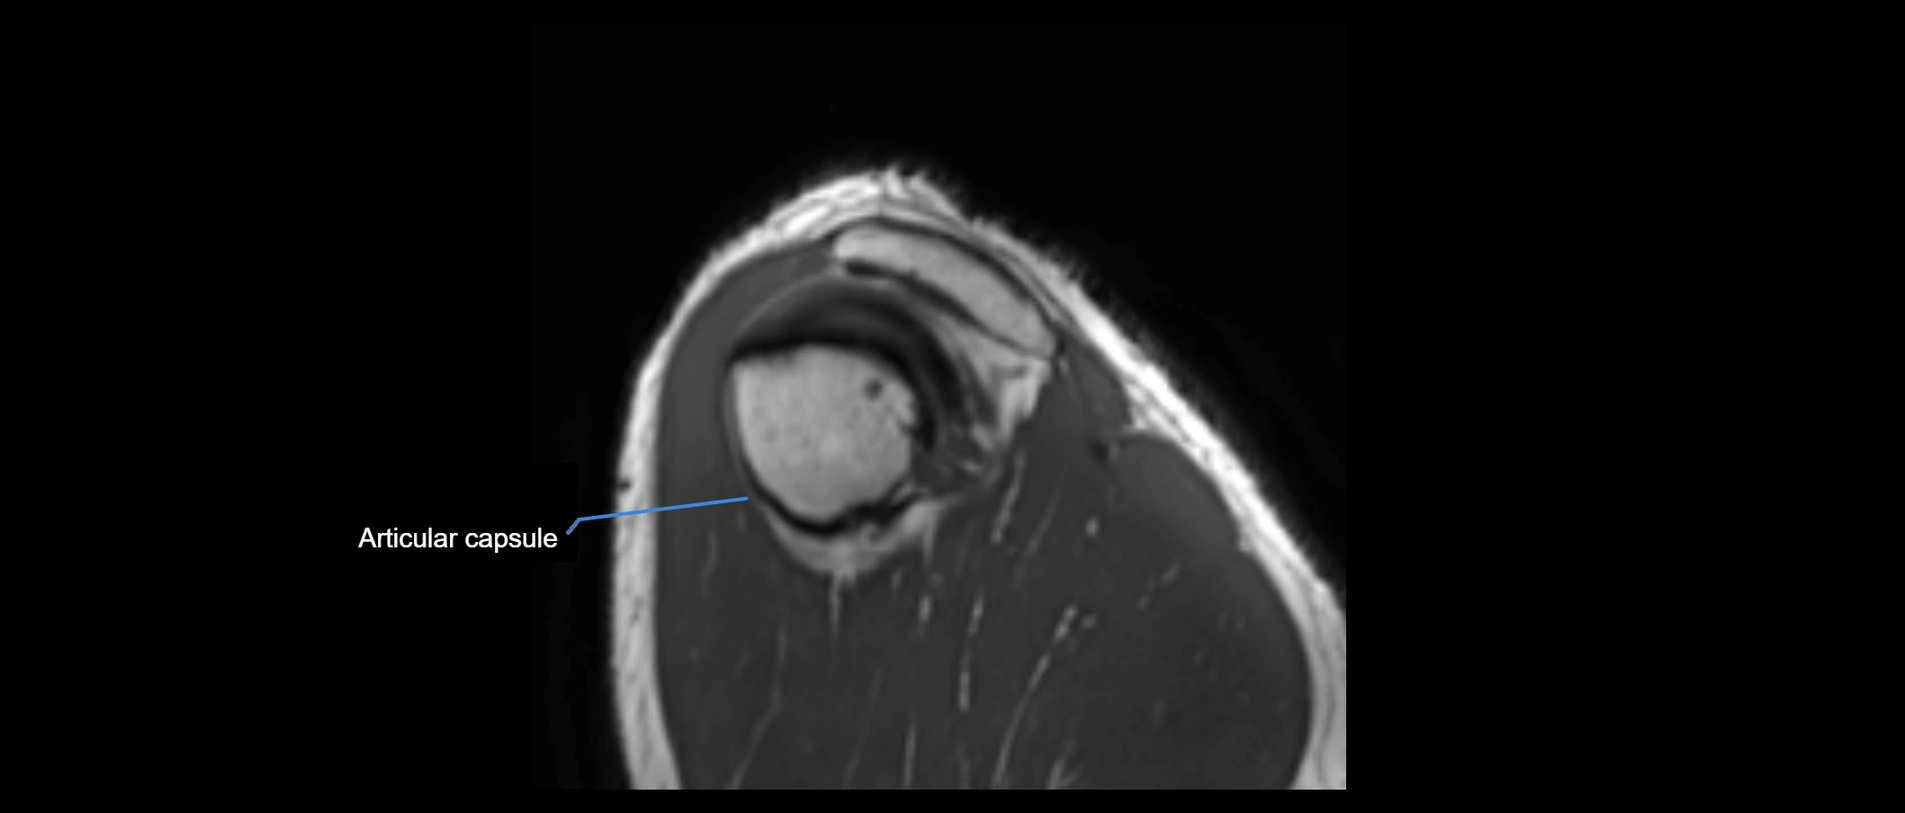

MRI images

image

• Proton Density Fat-Saturated (PD FS):

• Normal ligament: Low signal, uniform thickness.

• Partial tear or sprain: Bright signal or contour irregularity.

• Complete tear: Clear discontinuity with bright signal gap and joint effusion.

• Excellent for assessing joint capsule, coracoclavicular ligaments, and periarticular edema.